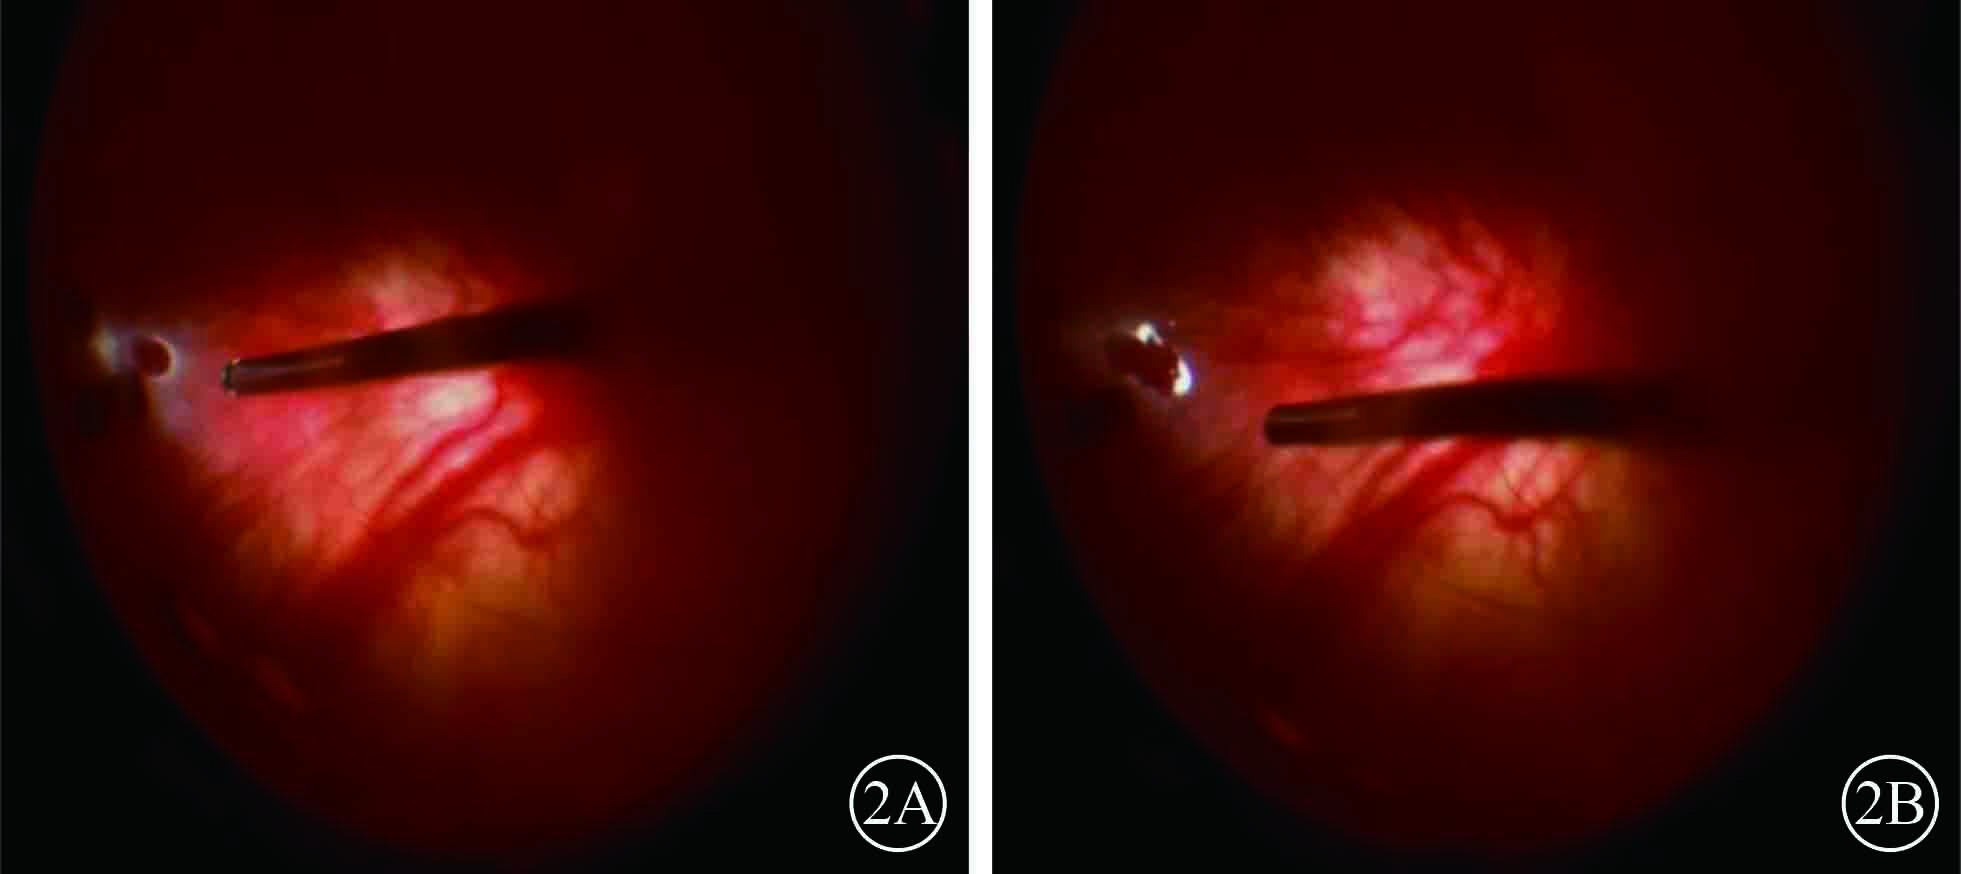

圖2

右眼手術中視頻剪輯像。2A. 8點時鐘位周邊視網膜圓形裂孔;2B. 電凝后視網膜裂孔邊緣呈白色外觀

圖2

右眼手術中視頻剪輯像。2A. 8點時鐘位周邊視網膜圓形裂孔;2B. 電凝后視網膜裂孔邊緣呈白色外觀

患者男,35歲。因體檢發現雙眼視網膜脫離1月余于2015年3月12日來我院眼科就診。患者自幼皮膚、毛發、虹膜無色素;雙眼視力差、畏光。否認外傷史、家族史。眼部檢查:右眼視力數指/30 cm,左眼視力0.1;雙眼矯正視力均無提高。雙眼眼瞼皮膚及睫毛均無色素;眼球水平震顫;角膜透明,瞳孔圓,虹膜半透明;晶狀體透明。雙眼眼底呈橙色。右眼全視網膜脫離,左眼0~8點時鐘位視網膜脫離(圖1);雙眼視網膜裂孔均窺不清。A型超聲檢查,右眼、左眼眼軸長度分別為26、28 mm。診斷:(1)雙眼孔源性視網膜脫離(疑似);(2)雙眼高度近視;(3)眼皮膚白化病。分別于2015年3月23日、5月11日行左眼、右眼視網膜復位手術。采用標準25G經睫狀體平坦部玻璃體切割手術。手術中見左眼視網膜裂孔分別位于 1、2、4、6點時鐘位,右眼裂孔位于8、11點時鐘位。先采用眼內電凝對裂孔邊緣進行標記,電凝處理后裂孔邊緣呈白色外觀(圖2);視網膜復位后,采用視網膜冷凍替代常規激光光凝對裂孔進行封閉;最后進行硅油眼內填充。雙眼均于手術后3個月行硅油取出手術。硅油取出后3個月,雙眼視網膜復位良好,眼底呈橙色,透見脈絡膜大血管(圖3);6個月,右眼視網膜復位良好,左眼下方視網膜再次脫離。于2016年2月1日再次行左眼視網膜復位手術、硅油填充。2016年12月27日隨訪,右眼視網膜復位良好;左眼硅油填充,下方視網膜仍有局部脫離(圖4)。

患者男,35歲。因體檢發現雙眼視網膜脫離1月余于2015年3月12日來我院眼科就診。患者自幼皮膚、毛發、虹膜無色素;雙眼視力差、畏光。否認外傷史、家族史。眼部檢查:右眼視力數指/30 cm,左眼視力0.1;雙眼矯正視力均無提高。雙眼眼瞼皮膚及睫毛均無色素;眼球水平震顫;角膜透明,瞳孔圓,虹膜半透明;晶狀體透明。雙眼眼底呈橙色。右眼全視網膜脫離,左眼0~8點時鐘位視網膜脫離(圖1);雙眼視網膜裂孔均窺不清。A型超聲檢查,右眼、左眼眼軸長度分別為26、28 mm。診斷:(1)雙眼孔源性視網膜脫離(疑似);(2)雙眼高度近視;(3)眼皮膚白化病。分別于2015年3月23日、5月11日行左眼、右眼視網膜復位手術。采用標準25G經睫狀體平坦部玻璃體切割手術。手術中見左眼視網膜裂孔分別位于 1、2、4、6點時鐘位,右眼裂孔位于8、11點時鐘位。先采用眼內電凝對裂孔邊緣進行標記,電凝處理后裂孔邊緣呈白色外觀(圖2);視網膜復位后,采用視網膜冷凍替代常規激光光凝對裂孔進行封閉;最后進行硅油眼內填充。雙眼均于手術后3個月行硅油取出手術。硅油取出后3個月,雙眼視網膜復位良好,眼底呈橙色,透見脈絡膜大血管(圖3);6個月,右眼視網膜復位良好,左眼下方視網膜再次脫離。于2016年2月1日再次行左眼視網膜復位手術、硅油填充。2016年12月27日隨訪,右眼視網膜復位良好;左眼硅油填充,下方視網膜仍有局部脫離(圖4)。

圖2

右眼手術中視頻剪輯像。2A. 8點時鐘位周邊視網膜圓形裂孔;2B. 電凝后視網膜裂孔邊緣呈白色外觀

圖2

右眼手術中視頻剪輯像。2A. 8點時鐘位周邊視網膜圓形裂孔;2B. 電凝后視網膜裂孔邊緣呈白色外觀